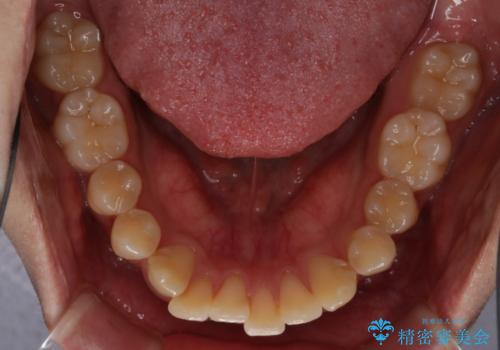

- 前歯のがたつきが気になるとご相談にいらした方です。左の奥歯の噛み合わせのズレも認められたため、インビザライン治療にて改善しました。

主訴である前歯のガタつきだけでなく、奥歯の噛み合わせからしっかり治療したため、治療期間が長めとなりました。患者様ご本人としては治療の途中で一時的にモチベーションが下がったこともあったようですが、最後まで頑張って続けて頂けたことで噛み合わせ及び見た目の改善を行うことが出来ました。